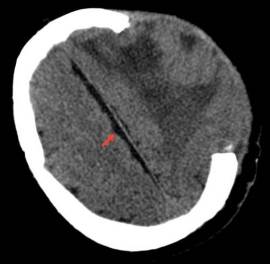

佩戴2周后硬膜下积液消失